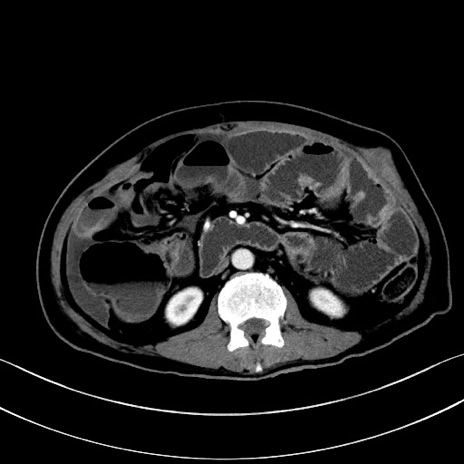

症例28(横断像)

【症例】60歳代男性

【主訴】嘔吐

【現病歴】胃癌にて胃全摘後。食思不振が悪化し、夜中に嘔吐することがある。

【既往歴】胃癌、胃全摘、脾摘、胆摘後

【データ】WBC 5900、CRP 10.56